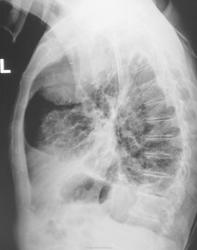

в фазе уплотнения с двух сторон. Справа, судя по размеру, туберкулома, отошедшая в мир иной.

Игорь Артурович!Т.е. туберкулома опорожнилась и сьежилась,скукожилась ???А вправом корне-россыпь кальцинатов.

+1. Только туберкуломы не отходят в мир иной, они спать ложатся

в ПТД, так у больного имеется вспышка туберкулезного процесса. См. рисунок. Стрелки указывают активные очаги. С уважением Nikolas

Конечно, мы направили, направили к фтизиатру..., но все изменения были расценены, как старые, и возбуждения у фтизиатра не возникло...

Совершенно не известный. Но, со слов пациента, стало известно, что 40 лет тому назад он состоял на учете, переболел туберкулезом, лечился и был снят с учета.

Но, прошло полтора года, и гражданина с "флюшки" опять "зацепили" и провели дообследование.